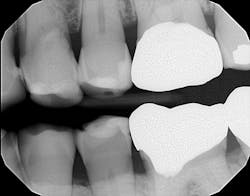

Radiographically, the first thing I noticed were the tabletopped occlusal surfaces (figures 1 and 2). Clinically, the same was evident, along with generalized wear facets on the posterior teeth (figures 3 and 4). The bite was deep (figures 5 and 6), and the lower anterior teeth had been worn down to half their original size. There were new ceramic crowns on nos. 21, 28, and 29. I also noted that there was an occlusal stop/resin on no. 13, but there was no significant effect on his occlusion as it was even on the right and left sides.